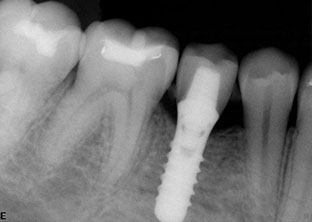

Dental implants

Dental implants have been used for decades to provide a stable support for missing teeth. Implants can be used to stabilize dentures, act as anchors for a bridge, or replace single teeth that are missing.

Implants are designed to be incorporated into the structure of the jawbone. A crown is then attached to the implant to function as a normal tooth. In most cases, implants take several months from placement to the final restoration(s). There is a period of healing while the implant becomes part of the body and stabilizes.